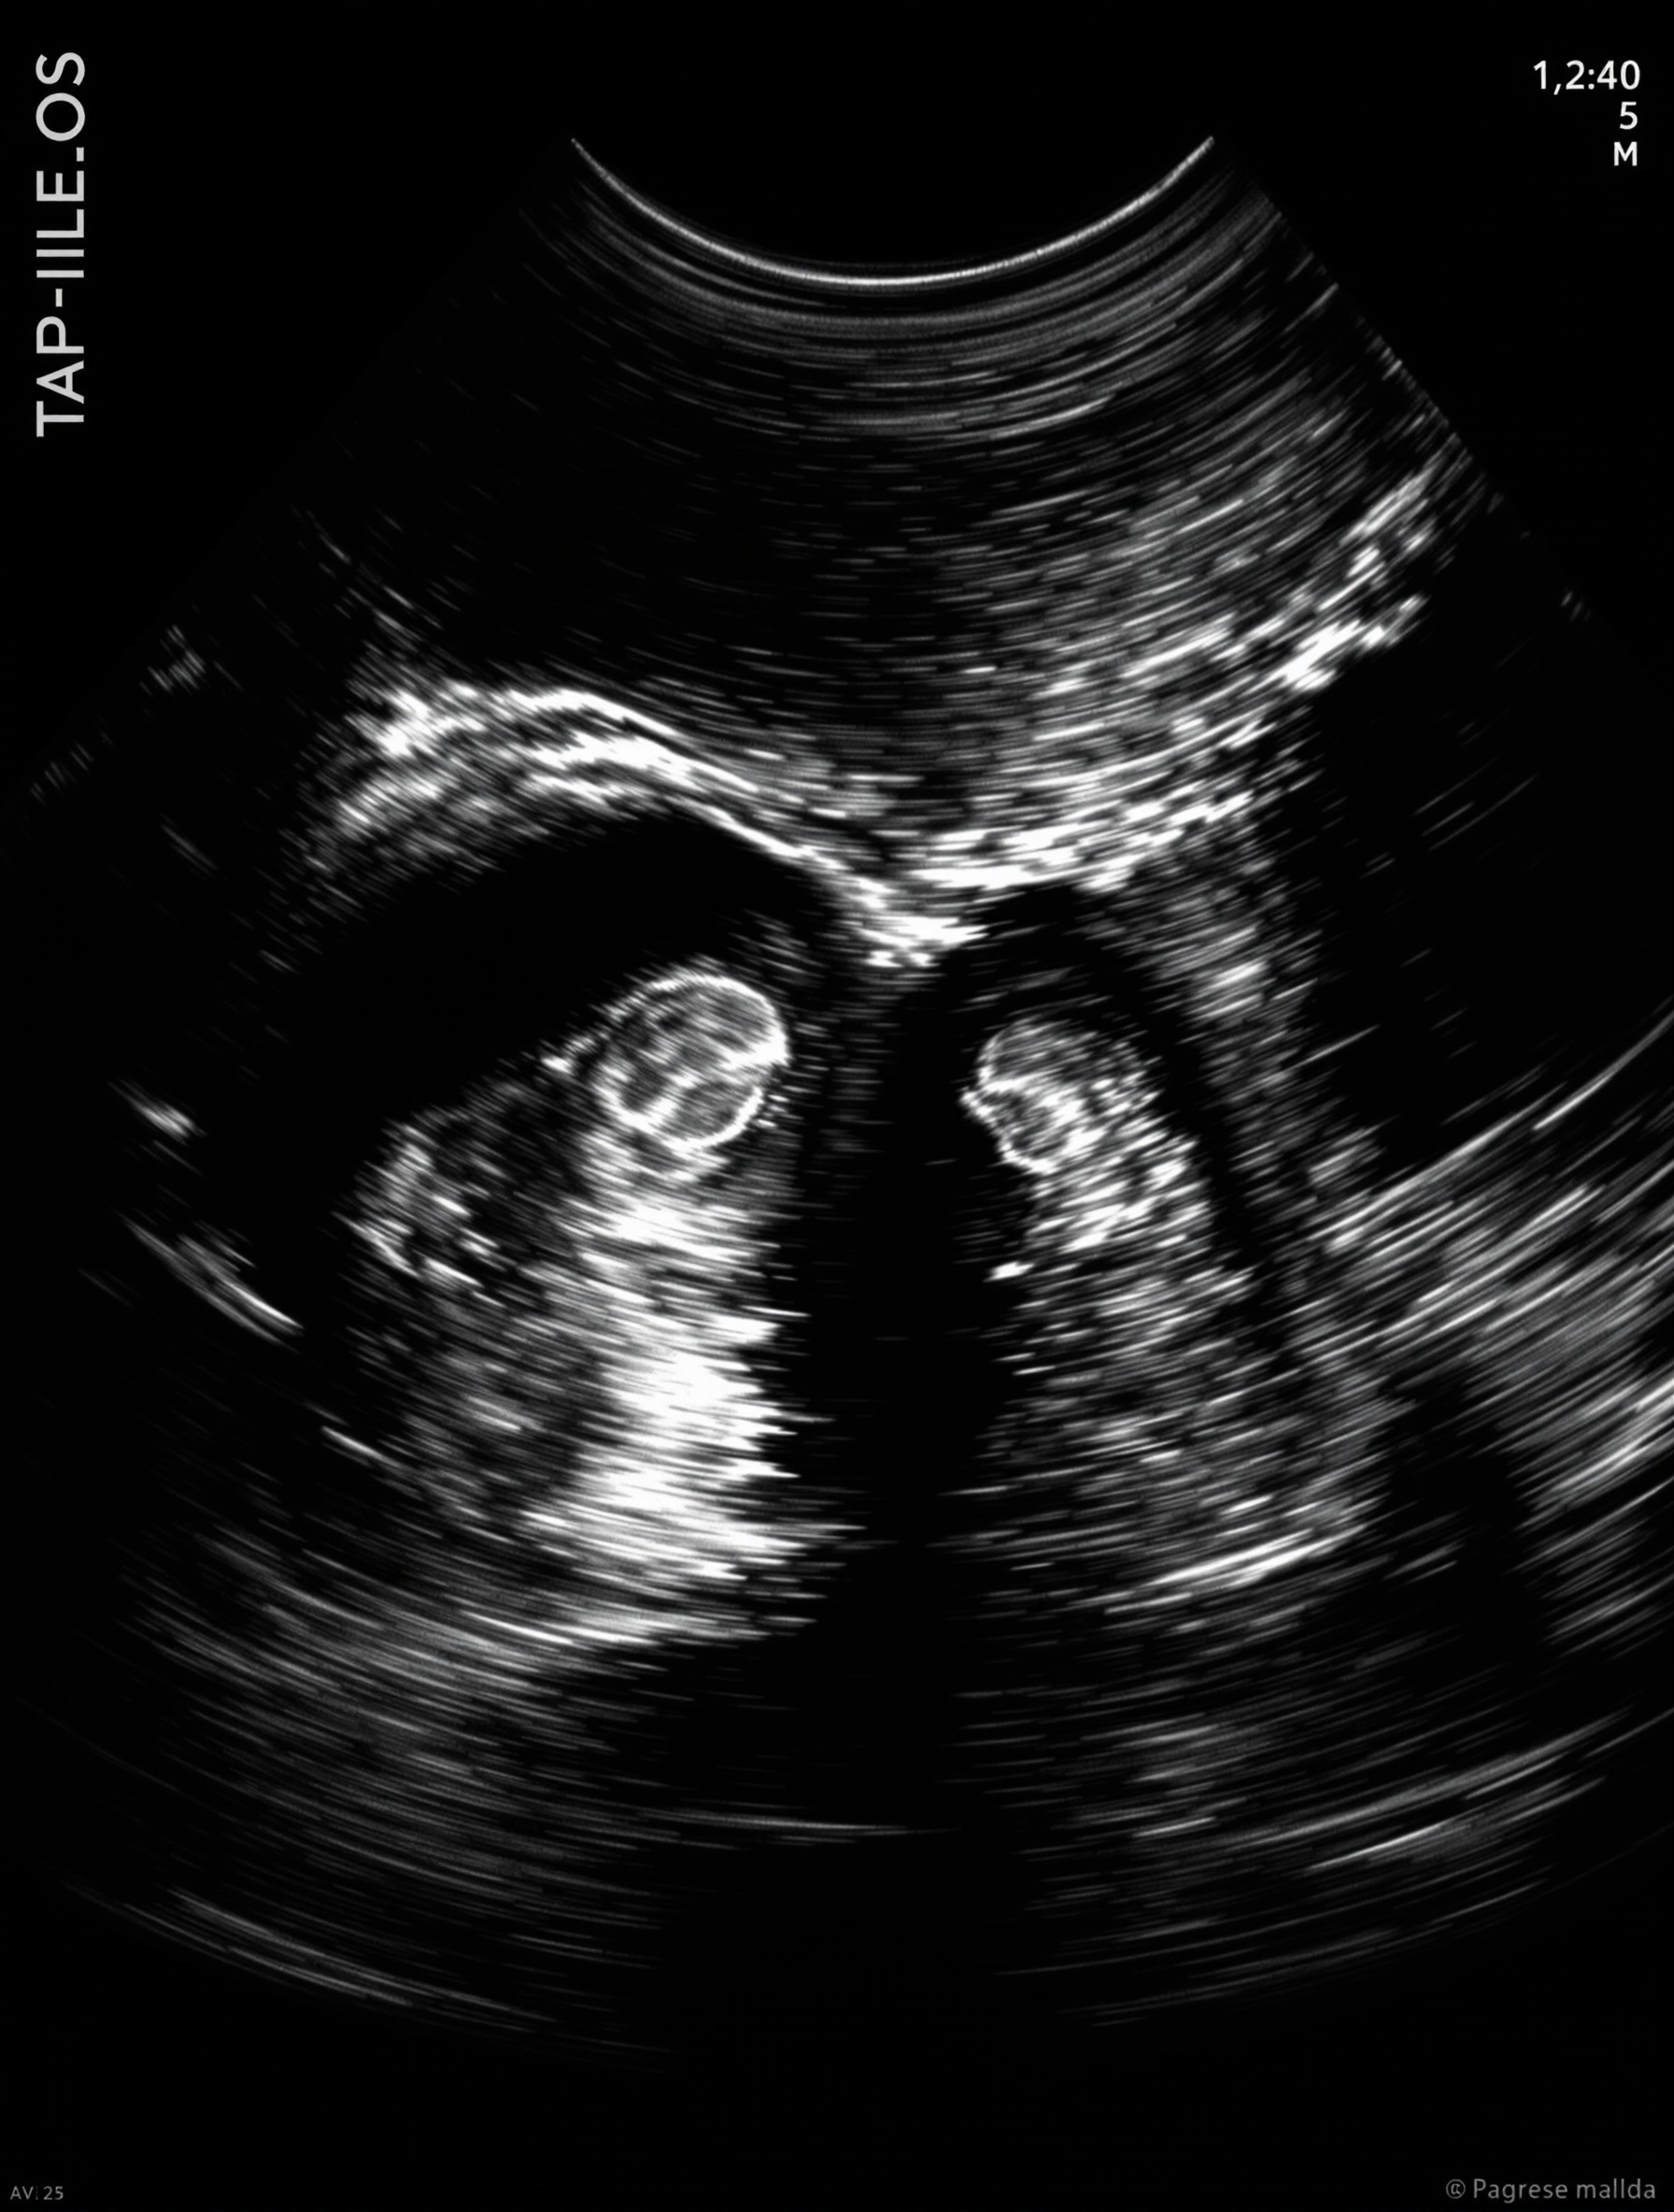

Le syndrome du jumeau perdu se manifeste chez des personnes issues d’une grossesse gémellaire où, sans souvent que les parents eux-mêmes en aient conscience, l’un des embryons — connu sous le terme de jumeau évanescent — disparaît au cours du premier trimestre. Les médecins parlent alors de "jumeau évanescent" lorsque le second fœtus cesse de se développer, laissant son frère ou sa sœur traverser seul(e) la gestation (Parents.fr).